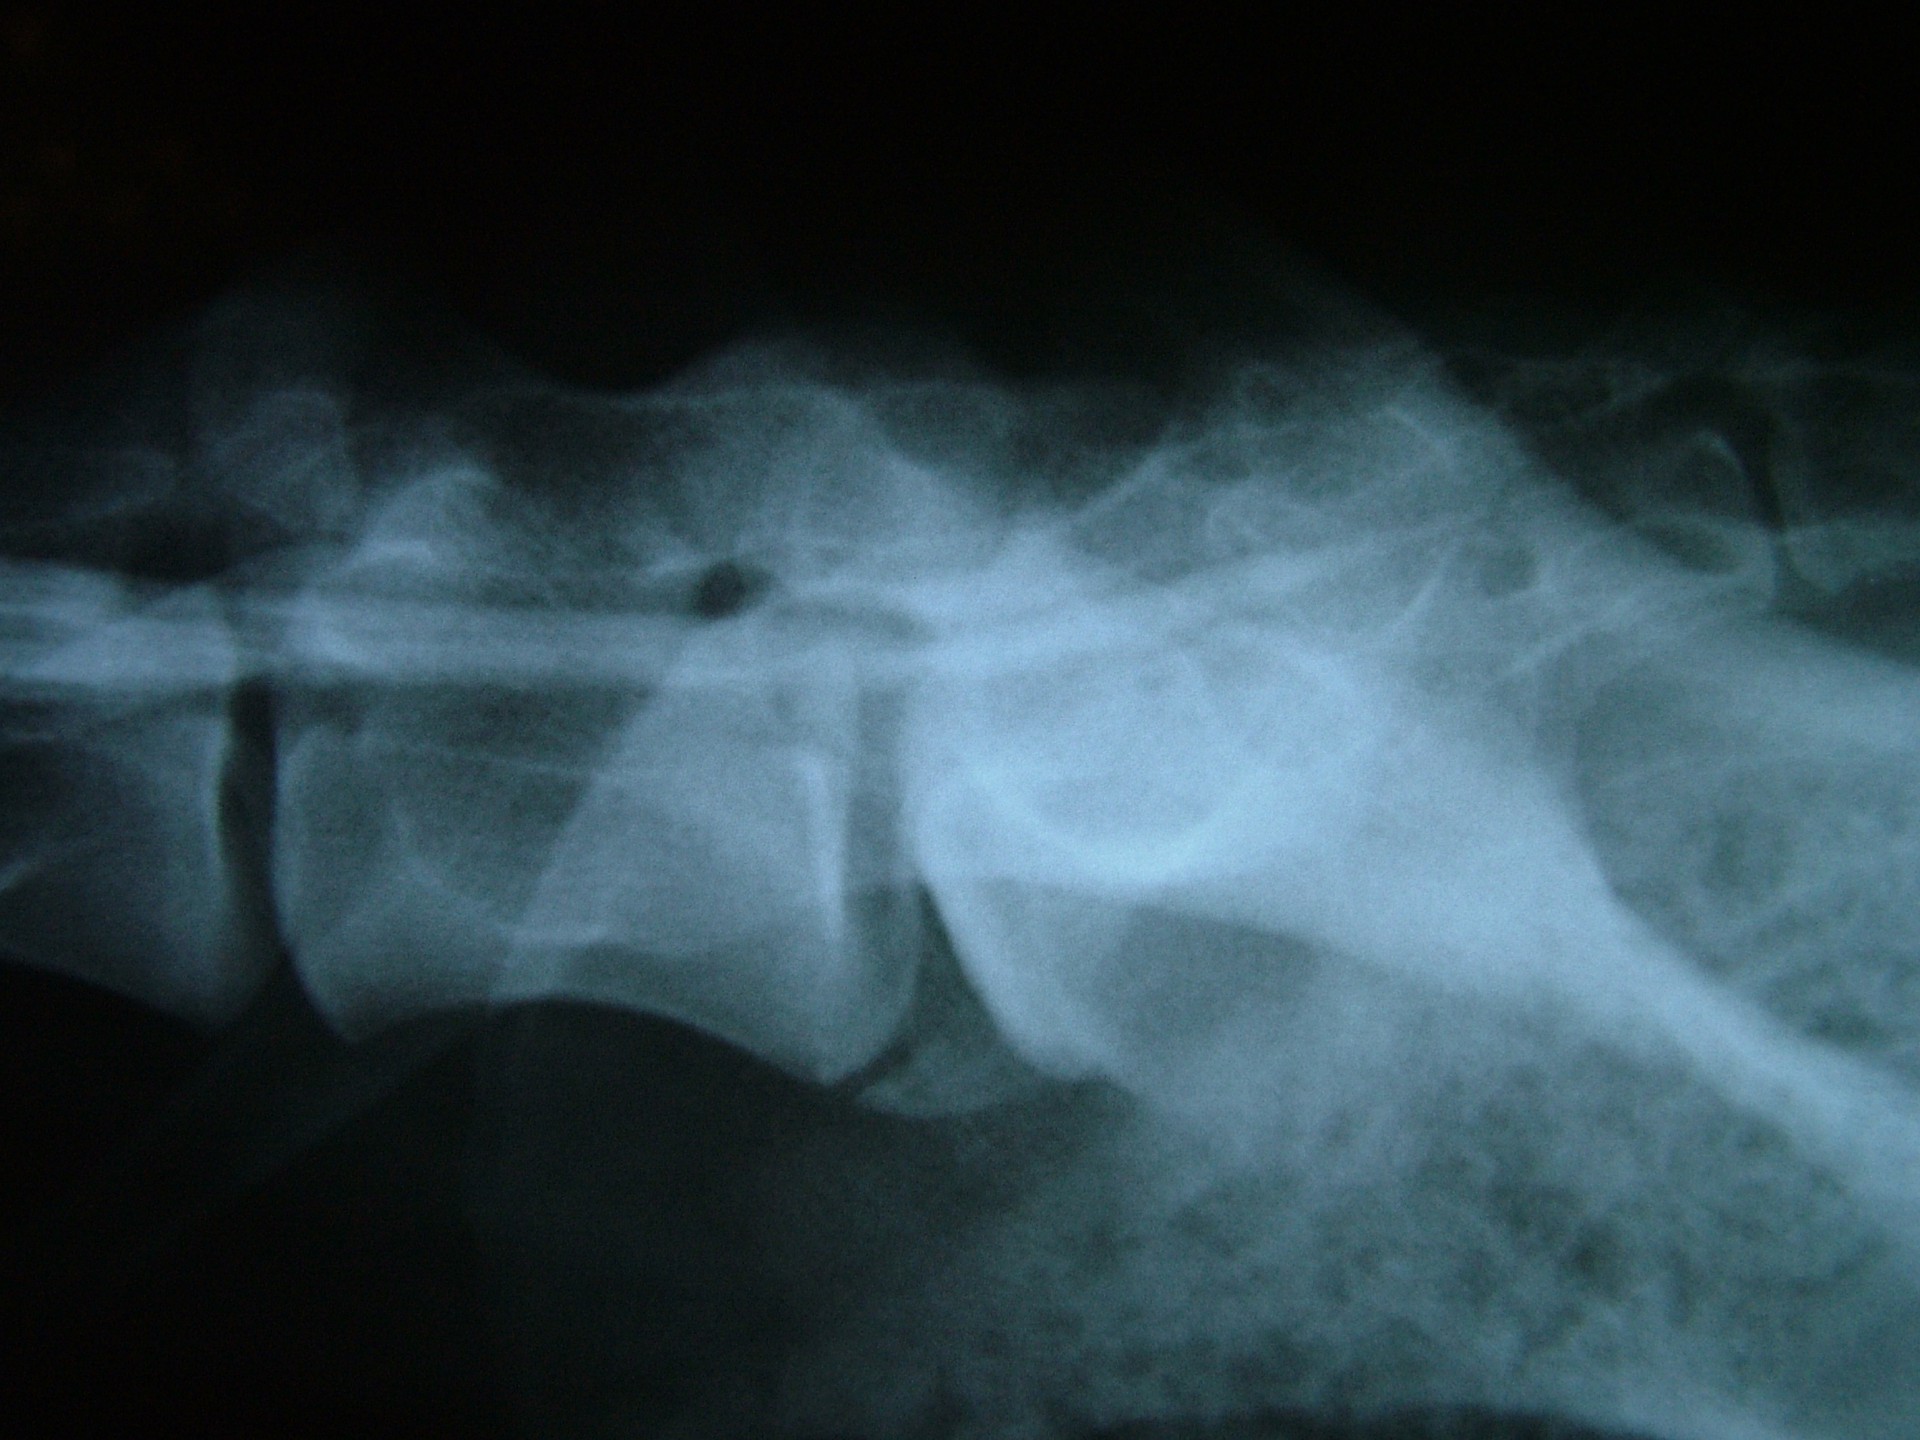

A C.E.C diagnosztikájának legfontosabb lépése a kórelőzmény megismerése után (hátulsó testfél gyengeség, rogyadozás, széklet-vizeletürítési problémák, fájdalom stb.) az alapos klinikai vizsgálat, mely során a gerinctájék fájdalmasságát, a hátulsó végtag reflexeit, a fájdalomérzet meglétét vizsgáljuk.Amennyiben a klinikai tünetek indokolják kiegészítő vizsgálatként elsősorban a röntgenvizsgálat jön szóba, mely során a gerincoszlop ezen szakaszáról oldalirányú felvételt készítünk.

Amennyiben a klinikai tünetek és az oldalirányú röntgenfelvétel alapján a C.E.C. alapos gyanúja felmerül további vizsgálatokkal kell kizárnunk egyéb gerincbetegségeket ill. megerősíteni a C.E.C. diagnózisát.

Az egyik ilyen vizsgálat a gerincfestés vagy myelographia, mely során a gerincvelőt körbevevő térbe (subduralis tér), az agy-gerincvelői folyadékba (liquor) röntgenkontraszt anyagot juttatunk és sorozatos felvételekkel ellenőrizzük annak áramlását. Ennek előnye, hogy a kontrasztanyag lefutása során az egyéb gerincszakaszok is kirajzolódnak, és ezek esetleges betegségeit is diagnosztizálhatjuk. A gerincoszlop hátsó szakaszáról 1db teljesen hajlított és 1 db teljesen nyújtott beállítású RTG felvételt készítünk. Ha a két felvétel között jelentős különbséget tapasztalunk a C.E.C. biztosan diagnosztizálható.A másik invazív diagnosztikai eljárás a durographia, mely során a röntgenkontraszt anyagot a durazsák körüli térbe (epiduralis tér) juttatjuk és így indirekt módon ábrázoljuk a gerincvelő esetleges összenyomatását. A vizsgálat során a kontrasztanyag telődési hiánya jelzi az összenyomatást és annak mértékét.A diagnosztika legmodernebb vizsgálati módszere az MRI vizsgálat, mely során altatásban, invazív beavatkozás nélkül kaphatunk átfogó képet a vizsgálni kívánt gerincszakaszról. Magyarországon állatorvosi diagnosztikai célra csak a Kaposvári Egyetem Diagnosztikai és Onkoradiológiai Intézetében működő berendezés használható.